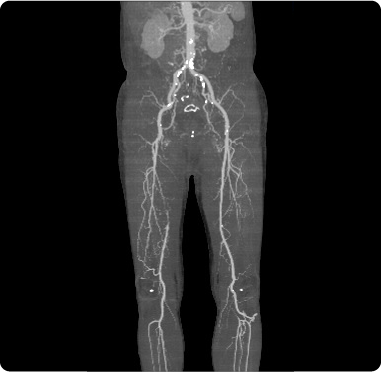

心臓の動脈に、動脈硬化がついて狭くなったり詰まったりすることがあるのと同様に、足の動脈にも動脈硬化がついて狭くなったり詰まったりする病気があります。閉塞性動脈硬化症という病気で、やはり高齢化や食生活の欧米化によって、患者数は増加しています。

典型的な症状としては、足が冷たい、ややしばらく歩くと足が張って痛くなるなどの症状があります。もっと重症になると、安静にしていても足が痛い、足の皮膚に潰瘍ができるなどの症状が出てきます。

腰部脊柱管狭窄症など整形外科の病気でも、ややしばらく歩くと足が張って痛くなるという症状が出ることがありますが、特に、タバコを吸う、糖尿病がある、高血圧がある、コレステロールが高いなどのリスク因子を有している患者さんの場合には、血管の病気を疑う必要があります。 外来で簡単に施行することができるABI検査で、閉塞性動脈硬化症があるかないかはだいたい診断することができます。ABI検査の結果で、やはり閉塞性動脈硬化症が疑われる場合には、下肢動脈エコー検査、あるいは下肢動脈CTを行って、狭窄部位を明らかにし、治療方針を決定します。

下肢閉塞性動脈硬化症の血管画像